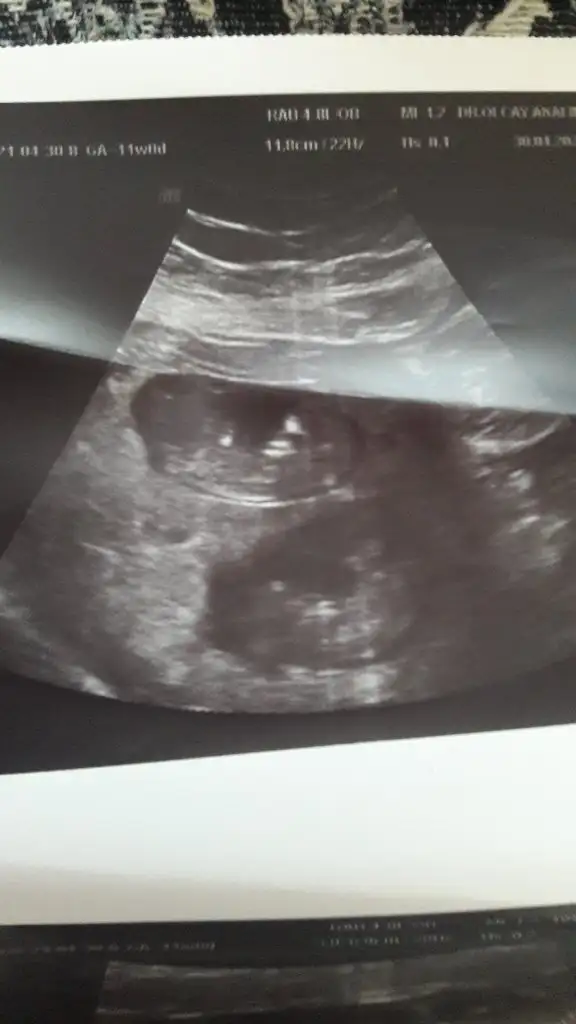

Canım bizede 12+5 de tahminde bulunurmusun karından usd dr bir tahminde bulundu ama net değil dedi🤗

• image.webp

image.webp

16 KB · Görüntüleme: 63

17,9 KB · Görüntüleme: 68